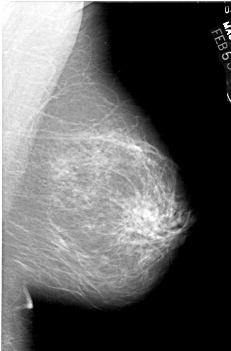

A_1443_1.LEFT_CC

RIGHT_MLO LINES 5956 PIXELS_PER_LINE 3916 BITS_PER_PIXEL 12 RESOLUTION 43.5 NON_OVERLAY